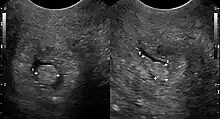

| Cervical polyp on ultrasound | |